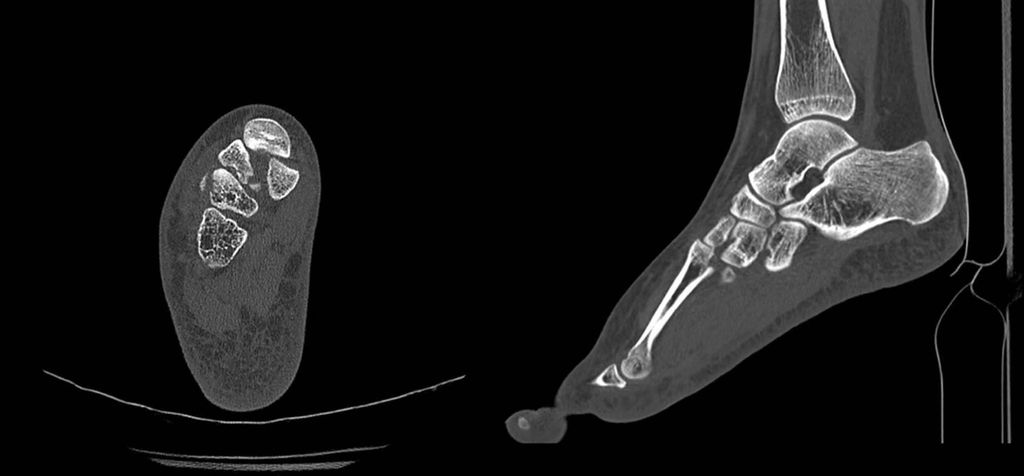

Häufig findet sich in der nativradiologischen Bildgebung kein absolut sicherer Hinweis auf eine Fraktur oder Luxation, da sich die knöchernen Strukturen in der Projektion überlagern. Hier sind entweder gehaltene Röntgenaufnahmen unter Bildwandler oder eine computertomografische Abklärung durchzuführen (Abb. 2).

Abb. 2: CT-verifizierte knöcherne Absprengungen und Subluxation zwischen dem Os cuneiforme mediale und dem metatarsalen Gelenk II des in Abbildung 1 im Nativröntgen dargestellten Fußes

Nun erfolgt die radiologische Überprüfung der Repositionsergebnisse unter Bildwandlerkontrolle, wobei sich unserer Erfahrung nach ein 3D-CT-Bildwandler bewährt hat. Meistens haben sich durch die Repositionsmanöver des I.–III. Tarsometatarsalgelenkes das IV. und V. Tarsometatarsalgelenk spontan mitreponiert; nur bei weiter bestehender Luxation ist eine offene Reposition durch einen zweiten Zugang notwendig. Auch hier werden die Gelenke mit Kirschnerdrähten in der Reposition gehalten. Anschließend erfolgt die temporäre Transfixation der Gelenke.